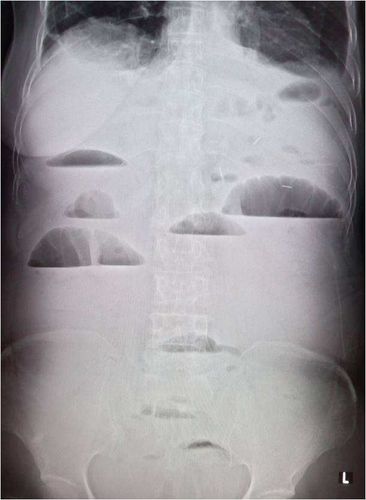

梗阻发生后的4~6小时,腹平片上即可见胀气的肠袢及多数气液平面.

肠梗阻的征象为腹部三个及以上高低不等呈阶梯状排列的气液平